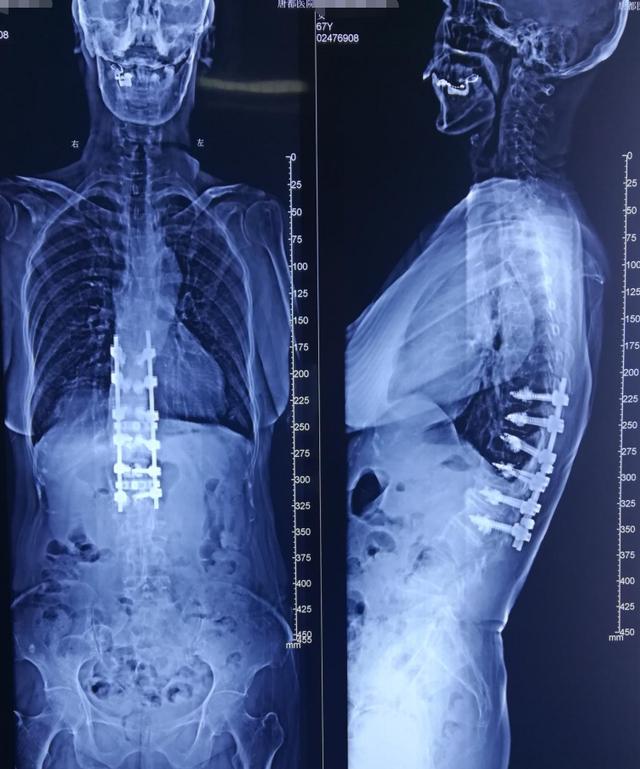

病例分享胸腰段脊柱后凸畸形

病例分享:脊柱后凸畸形矫形术